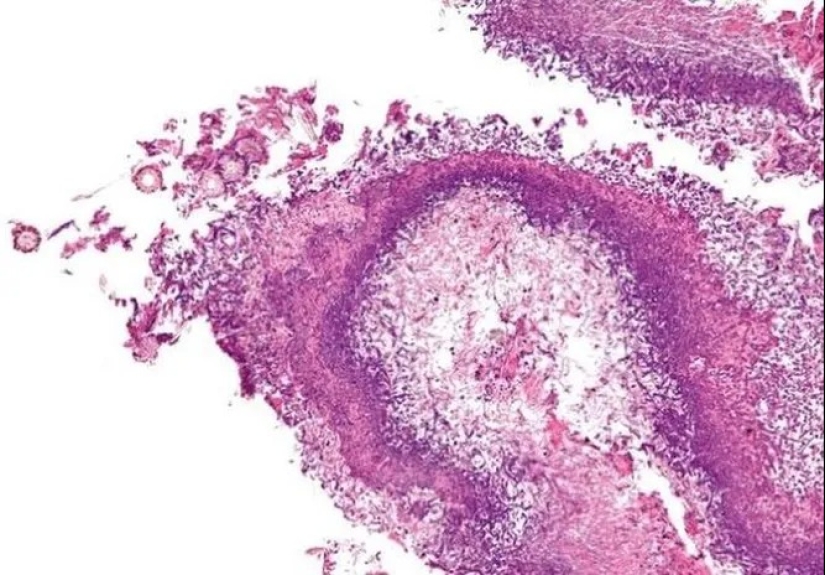

Staphylococcus is a large bacterial genus comprising a large number of species. Staphylococcus aureus, or Staphylococcus aureus is one of the most pathogenic of them.

Staphylococcus aureus can cause pneumonia, meningitis, toxic shock, sepsis and other very unpleasant diseases. At first, the doctors used penicillin to fight this bacteria. But over time, mutations have led to most strains of resistance, and antibiotics have almost lost their effectiveness. Staphylococcus aureus is a problem of developed countries and actively thriving in medical institutions.